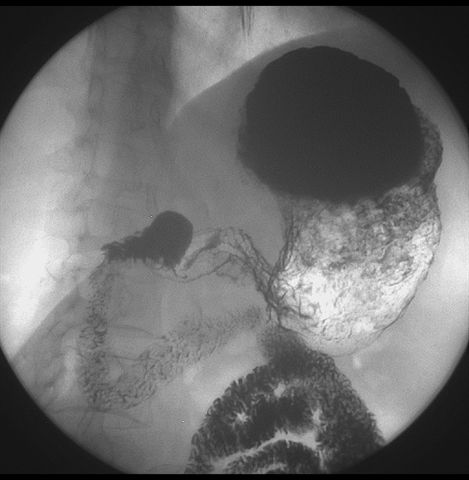

标题: X6872:F,69y,胃部不适。

胃窦至幽门段胃壁僵硬,扩张受限,局部纠集粘破坏,呈杵状。提示溃疡癌变可能性大。

胃窦癌可能性大,建议胃镜活检。钡剂太稀,吃的有点多。

支持考虑胃窦癌可能,胃内滞留液太多,胃窦部僵硬。

瀑布型胃,胃粘膜那是一个乱,窦部充盈不好,第16幅窦部粘膜反倒又很顺,先定个胃炎胃窦炎胃窦癌待排之类,建议进一步作胃镜检查。

胃窦部见钡池影,局部粘膜紊乱,纠集呈杵状改变,胃壁扩张受限,胃窦癌可能性大,建议胃镜检查.

胃窦部管腔扩张度较差,形态略有改变,胃窦粘膜显示欠佳,胃窦部占位可能性大,结合胃镜活检。

北京肿瘤医院胃镜诊断皮革胃。